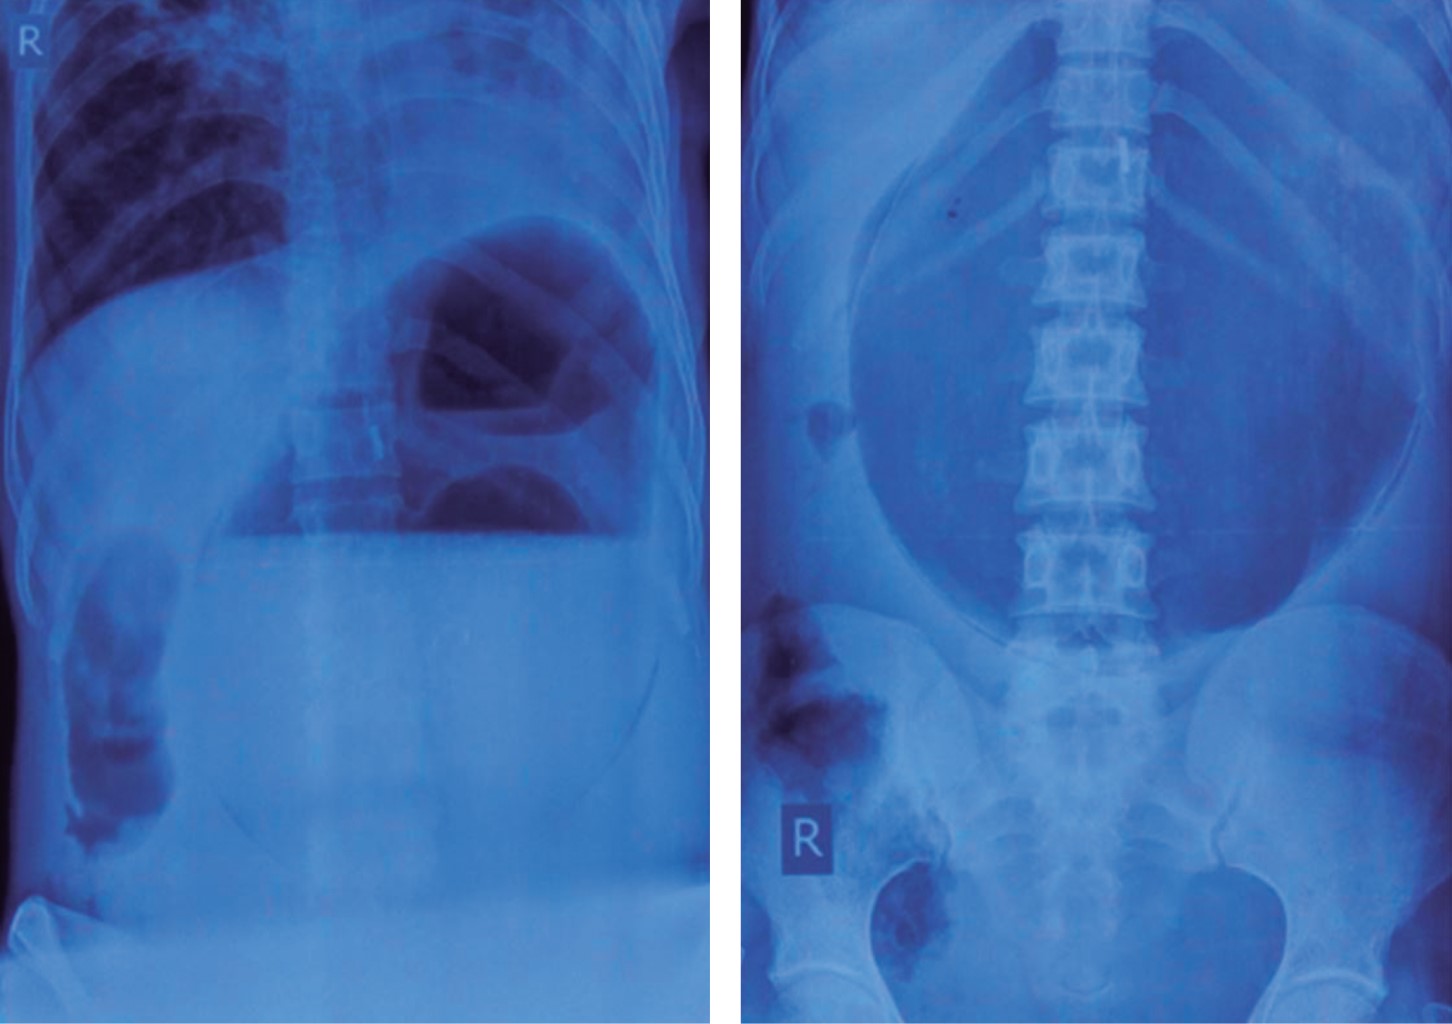

El VG es una condición de baja frecuencia con una tasa alta de mortalidad (30-50%), por lo que es necesario conocer la patología y su presentación para realizar un diagnóstico e intervención oportunos.2,7 La clasificación utilizada es la de Singleton (Figura 2):

Tipo I. Órgano-axial: rotación del estómago sobre su eje longitudinal, el cual se extiende de la unión gastroesofágica al píloro. El antro gira en sentido opuesto al fundus gástrico. Es la entidad más común (60% de los casos).

Tipo II. Mesentérico-axial: rotación del estómago en su eje horizontal que pasa a través de las curvaturas mayor y menor. Se presenta como una condición idiopática con síntomas crónicos o intermitentes (30% de los casos).

Tipo III. Mixto: combinación rotación órgano-axial y mesentérico-axial, es una entidad extremadamente rara (2% de los casos).

Tipo IV. Sin clasificar (8%).

Figura 3